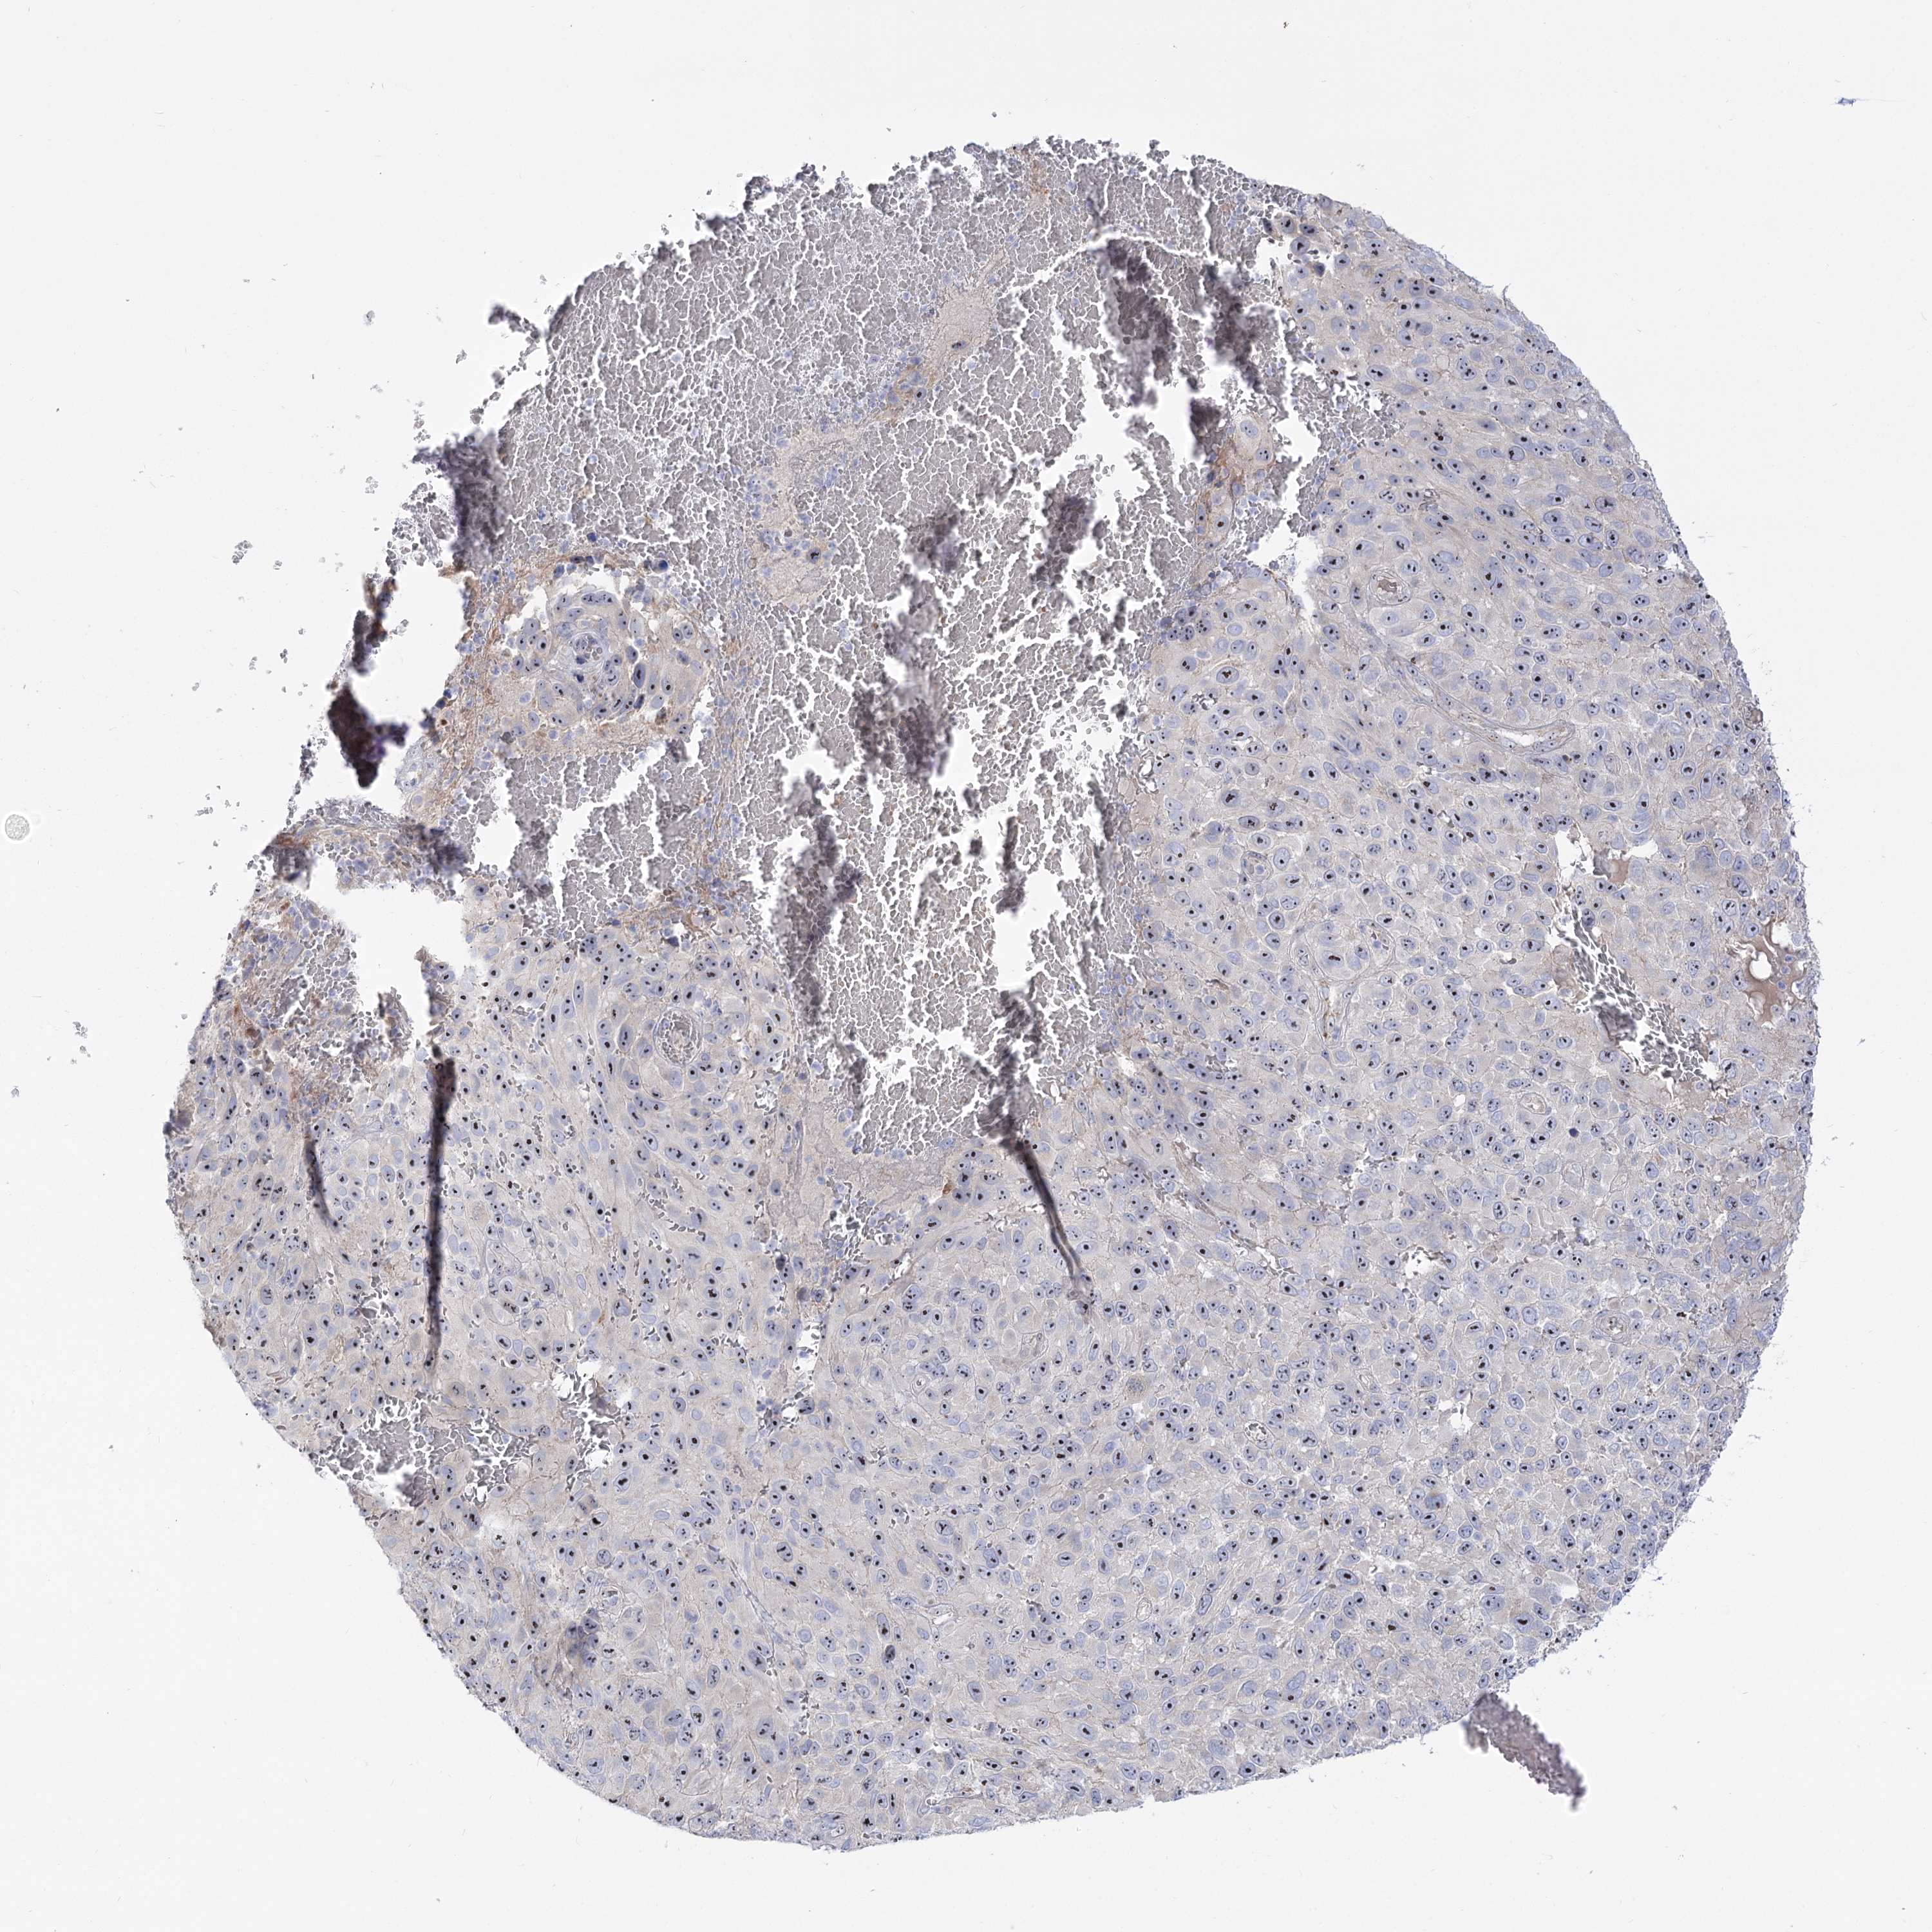

MELANOMA - Protein expressioni

A mouse-over function shows sample information and annotation data. Click on an image to view it in a full screen mode. Samples can be filtered based on level of antibody staining by selecting one or several of the following categories: high, medium, low and not detected. The assay and annotation is described here.

Note that samples used for immunohistochemistry by the Human Protein Atlas do not correspond to samples in the TCGA dataset.

Antibody stainingi

Antibody staining in the annotated cell types in the current human tissue is reported as not detected, low, medium, or high, based on conventional immunohistochemistry profiling in selected tissues. This score is based on the combination of the staining intensity and fraction of stained cells.

Each image is clickable and will lead to virtual microscopy that enables deeper exploration of all samples and also displays staining intensity scores, fraction scores and subcellular localization as well as patient and tissue information for each sample.

Antibody HPA038208

Antibody HPA038209

Staining

High

Medium

Low

Not detected

Intensity

Strong

Moderate

Weak

Negative

Quantity

>75%

75%-25%

<25%

None

Location

Nuclear

Cytoplasmic/membranous

Cytoplasmic/membranous,nuclear

Malignant melanoma, NOS

Malignant melanoma, Metastatic site